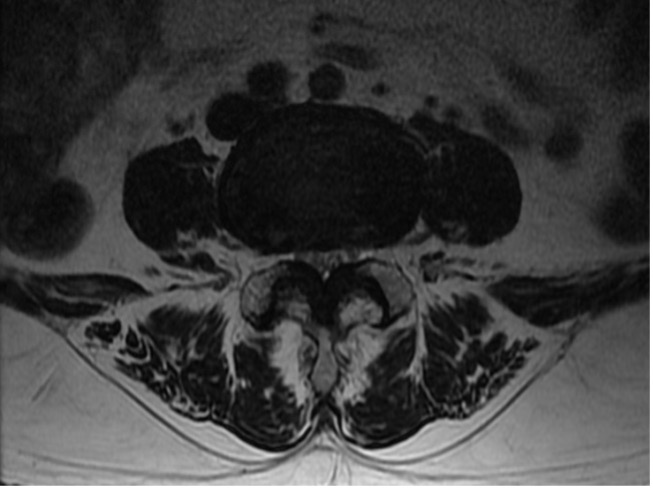

척추관협착증

척추관협착증이란

어떤 원인으로 척추 중앙의 척추관, 신경근관 또는 추간공이 좁아져 허리의 통증의 유발하거나 다리에 여러 복합적인 신경증세를 일으키는 질환

입니다.

디스크를 구성하는 수핵과 섬유륜에 퇴행성 변화가 일어나고 척추관을 구성하는 뼈와 인대 등이 두꺼워져 척추 뼈가 어긋나는 경우 척추 신경을 눌러 통증을 일으킵니다.